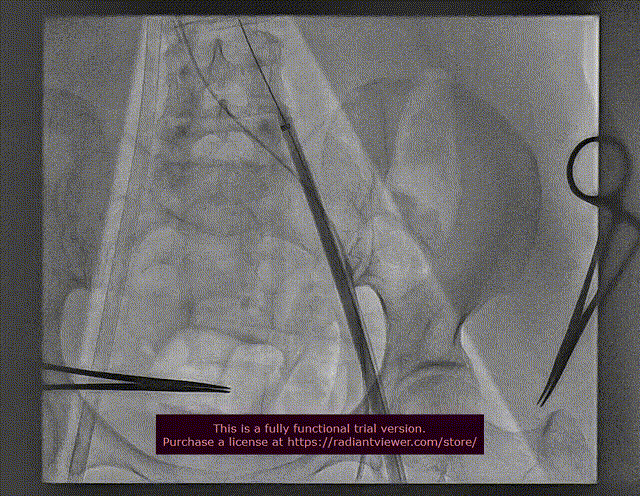

7.可调弯导管协助猪尾导管跨二尖瓣

二尖瓣跨瓣

8. 小球囊预扩房间隔和球囊系统预跨二尖瓣生物瓣

球囊扩张房间隔

球囊预跨二尖瓣